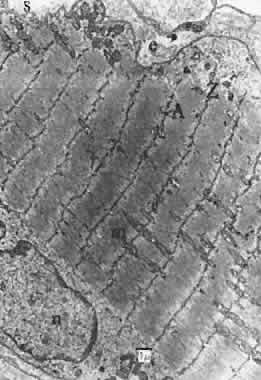

We know from human EMG study that eye muscles are constantly active when awake; therefore, they need much stamina. Eye position can be accurately maintained; this requires fine control. Rapid eye movements are possible: this requires high speed of muscle contraction. These attributes—precision, speed, and stamina—are physiologic properties of a motor unit reflected in the structure of the muscle fibers that comprise it. Using various histologic criteria, anatomists are able to subdivide at least five types of muscle fibers in the extraocular muscles.25 MUSCLE LAYERS Almost all investigators find that the extraocular muscles of mammals are divided into two layers to some extent: a global or central layer, next to the eye, and a superficial or orbital layer confined to the posterior two thirds of the rectus muscles and less evident in oblique muscles. This layering is much less obvious in humans than lower species (Fig. 17). The orbital layer has a high capillary density and generally contains small fibers. Scott and Collins confirmed that, in humans, fibers that are active constantly for fixation near the primary position are predominantly in this layer.26 By the classification of Alvarado and Van Horn in cat, the orbital layer contains two fiber types.27 Both are relatively small, rich in mitochondria, and contain some lipid vacuoles. About 60% to 70% of the cells are singly innervated with good sarcoplasmic reticulum content, which allows rapid calcium ion changes with each contraction, and about 30% to 40% are multiply innervated slower fibers.

The global layer contains one type of multiply innervated fiber and three types of single innervated fibers of varying size, mitochondrial supply, and sarcoplasmic reticulum content. Type 1 is a large, pale, relatively mitochondria-free type rich in endoplasmic reticulum. This should be a very fast but readily fatigued fiber, good for saccades and for short periods of extreme gaze. These fibers constitute about 30% to 40% of the total number, but they occupy about 60% of the core area and thus contribute importantly in terms of strong but temporary force production. Types 2 and 3 are progressively smaller and contain increasing amounts of mitochondria and probably decreasing amounts of endoplasmic reticulum. These would be more fatigue resistant and slower in response than those that contain a great deal of cytoplasmic reticulum. MUSCLE FIBER ORIENTATION The muscle fibers are mostly parallel, but some side-to-side and end-to-side junctions of muscle fibers exist, creating a network within the global layer. Many fibers thus terminate before the end of the muscle; a cross section at the center shows more fibers than cross sections near either end. Oh and Demer have recently counted the fibers in the rectus muscles of monkeys and humans and confirm this restriction of the orbital layer to the posterior two thirds of the muscle.28 Surprising was the finding of insertion of some of these orbital fibers onto the fibromuscular tissue (“pulley”) in Tenon's fascia near the anterior one third of the muscle. FASCIA IN MUSCLES The endomysium surrounding these fibers contains substantial elastic tissue. The perimysium surrounding groups of muscle fibers contains more collagen fibers. Within this area run the small vessels and nerves to the muscle. These collagen fibers run along the length of the muscle; thus, their shortening by inflammation, scar or lack of being stretched by antagonist contraction (e.g., in paralysis) results in stiffening and restriction of eye movement, a common clinical problem. MUSCLE CONTRACTION In Figure 18, the muscle is diagrammatically dissected into its components. The heavy filaments are myosin; the thin filaments, a double helix of actin with additional proteins, tropomyosin, and troponin. The sliding of these filaments past one another provides length change, especially apparent in Figure 19. As thick and thin filaments of the muscle fiber slide past one another, the bridges between these filaments maintain the strength of the muscle. If there were many crossbridges, there would be more force, and if there were fewer crossbridges, there would be less force, as seen in isometric testing. In Figure 20, one can see that as the muscle is normally stretched, the number of cross bridges being effectively used maximumizes and then gradually diminishes as further stretching occurs. Unlike many muscles that work over a large range, extraocular muscles work almost entirely in the region from 1 to 2.2; that is, the rather linear slope to the left of the peak of tension. To work within this range, sarcomeres of muscles cannot be greatly stretched or compressed from their normal length of about 2.3 μm. When muscles are maintained at a stretched or shortened length for weeks or months, they respond by adding or removing sarcomeres to regain this length of 2.3 μm. Muscles so shortened become stiff also and cannot be distinguished mechanically from fascial or fibrotic contraction.29 DIFFERENCES IN TENSION Both singly and multiply innervated types of eye muscle fibers are composed of thick and thin filaments of about the same length. Thus, it is not surprising that they give about the same total force for each cross-sectional area.30 THE T SYSTEM How can a wave of depolarization sweep through an eye muscle and cause a twitch in 2 msec? Invaginations of the muscle membrane, the sarcolemma, extend into the muscle fiber in a direction transverse (t) to the axis of the fibrils, carrying the wave of polarization into the muscle itself. The sarcoplasmic reticulum that stores calcium necessary for activation is associated directly with these transverse tubules. Much T-system and sarcoplasmic reticulum is present in eye muscles to allow very rapid contraction frequencies up to 400 Hz. MITOCHONDRIA Mitochondria provide power to the muscle by oxidative phosphorylation. Because muscle contraction is powered by dephosphorylation of adenosine triphosphate, mitochondria are one source of energy. Thus, the more mitochondria present, the more power and stamina are provided. The extraocular muscles have an extremely high content of oxidative enzymes associated with the mitochondria. SINGLE AND MULTIPLE INNERVATION In certain eye muscle fibers, the filaments are separated into bundles. Obvious under light microscopy, this fibrillar pattern (Fibrillenstruktur) is generally associated with rapid, twitch-type contraction. A horizontal view of such a fiber (Fig. 21) reveals the extensive mitochondrial involvement and the differentiation into small bundles. Most of these fibers have single nerve innervation by only one motor endplate. Such a fiber is adapted for rapid, short-term use. In other fibers, the fibrils are not divided much into separate bundles, giving a rather uniform field of distribution (Felderstruktur). Some of these muscle fibers contract only in local areas of the muscle by local innervation around multiple nerve endings along the fiber, without an overall depolarization and twitch. In Figure 22, such a fiber is seen in cross section, again emphasizing the lack of separation into myofibrils. Such fibers would be less capable of high frequence contraction but more capable of slow, steady, stamina-oriented tasks. BLOOD FLOW AND FATIGUE Blood flow in the extraocular muscles must be exceedingly high to account for the rapid metabolism. Indeed, average blood flow per gram of extraocular muscles proportionally to that of other skeletal muscles and was second only to myocardium.31 Eye muscles are very resistant to fatigue under laboratory conditions. Extreme gaze to one side for several minutes, however, gives rise to unstable fixation in humans (end-gaze nystagmus). This is unequal in the two eyes, so it appears to be a fatigue of the muscles or motor units rather than of gaze function. CHANGES IN EXTRAOCULAR MUSCLE WITH AGE AND DISEASE Miller found alterations in staining characteristics, occasionally degenerating nerve fibers, and disturbance of the orderly fiber alignment and direction of human muscles after age 30.32 With age, the collagen fibers within the muscle itself increased. As motor nerve fibers drop out with neuron death, the remaining nerve fibers send sprouts to form new neuromuscular endings on the denervated muscle fibers. This process preserves muscle strength with aging. A similar sprouting in partial nerve damage leads to prolonged recovery with large motor units. The different types of muscle fiber are probably susceptible to diseases at varying rates. For example, muscular dystrophies associated with mitochondrial abnormalities should especially involve extraocular muscles. Cogan and colleagues have proposed a susceptibility difference seen also in myasthenia gravis.33 |